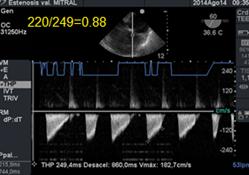

La cuantificación del área valvular se realiza por planimetría directa o por el Tiempo de Hemipresión(THP). Este método desarrollado por la Dra. Hatle , establece que el tiempo de caída de la presión diastólica pico a la mitad de su valor inicial, está inversamente relacionado con el área valvular mitral (AVM) :

AVM=220/THP (donde 220 es una constante empírica).(35)(36)

El tiempo de hemipresión (THP), (Figura 21) también está relacionado con el gradiente inicial y la compliance ventricular. Su medición es confiable, sencilla y rápida.

Figura 22 con Doppler Continuo medición y cálculo del área mitral a través del tiempo de hemipresión. Estenosis severa.